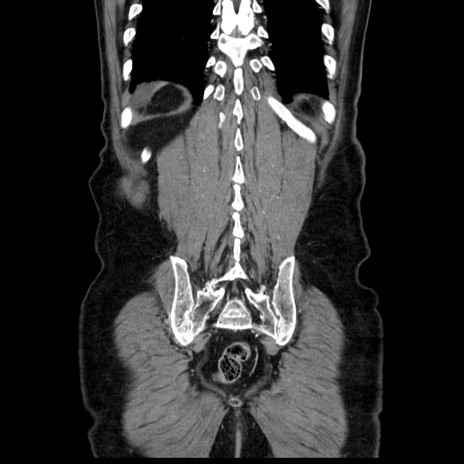

症例30(冠状断像)

【症例】80歳代男性

【主訴】臍周囲痛

【現病歴】約6時間前から臍下部痛が出現。次第に腹部膨隆・背部痛も生じてきたため来院。背部痛の場所は変化しない。

【身体所見】意識清明、BT 36.3℃、BP  131/87mmHg、P 87bpm、SpO2 100%(RA)、臍周囲自発痛・圧痛あり、反跳痛なし、自発痛部位に一致して板状硬あり、腹部膨隆、腸雑音減弱、CVA tenderness両側陰性。

【データ】WBC 19600、CRP 0.33